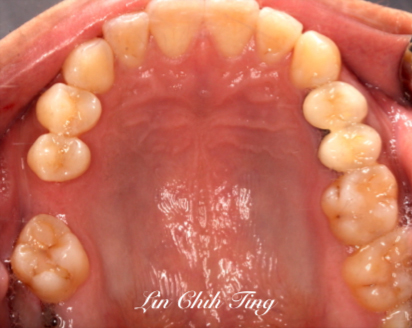

矯正治療過程

治療中

植牙治療過程

治療前

治療後